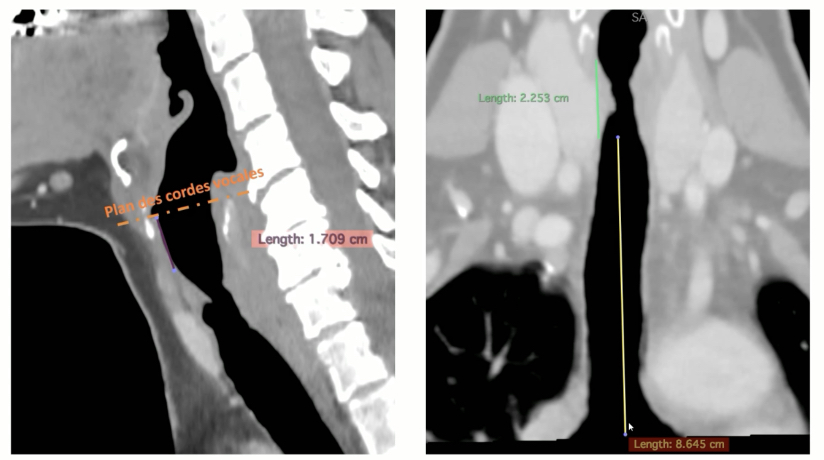

Mesures Utiles

- Distance aux cordes vocales

- Longeur de la sténose

- Distance à la carène